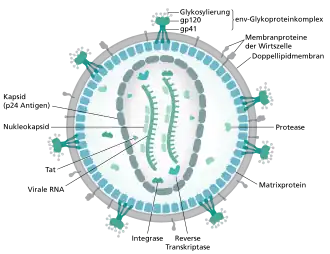

Das Viruspartikel (Virion) hat einen Durchmesser von etwa 100 bis 120 Nanometer und ist damit für ein Virus überdurchschnittlich groß, jedoch deutlich kleiner als zum Beispiel Erythrozyten (Durchmesser 7500 Nanometer). Umgeben ist das umgangssprachlich auch als „AIDS-Virus“ bezeichnete HIV von einer Lipiddoppelschicht, die bei der Knospung von der menschlichen Wirtszelle abgetrennt wurde.[11] Dementsprechend befinden sich verschiedene Membranproteine der Wirtszelle in der Virushülle, beispielsweise HLA-Klasse-I- und -II-Moleküle sowie Zelladhäsionsmoleküle.

Ebenfalls eingebettet in diese Hülle sind pro Virion etwa 12 bis 16 sogenannte Spikes (dt. ‚Dornen‘), ca. zehn Nanometer große virale Glykoproteinkomplexe (envelope, Env); die Dichte der Spikes ist somit recht niedrig, hätten doch 73 ± 25 dieser Fortsätze auf der Oberfläche eines HIV-Partikels Platz. Ein HIV-Spike ist ein Heterodimer und besteht daher aus zwei Untereinheiten: Je drei Moleküle des externen Oberflächen-(englisch surface)-Glykoproteins gp120 sind nicht-kovalent an drei Moleküle des transmembranen Hüll-(englisch envelope)-Glykoproteins gp41 gebunden.[12][13][14] Die Bezeichnungen spiegeln deren Molekülmasse in Kilodalton wider.[11] Gp120 ist für die Bindung des Virus an die CD4-Rezeptoren der Zielzellen von entscheidender Bedeutung.

Mit der Innenseite der Membran sind die durch gag codierten Matrixproteine p17 assoziiert. Im Inneren des Virions findet sich das Viruskapsid, das aus den durch gag codierten Kapsidproteinen p24 aufgebaut ist, deren Struktur schrittweise 1996[15] und 1997[16] aufgeklärt wurde. Das Kapsid besteht aus etwa 1500 Kapsidproteinen und nimmt dabei eine Fulleren-ähnliche, konische Struktur ein, dieses Strukturmodell wurde erstmals 1999 vorgeschlagen.[17] 2013 wurde mittels Kryoelektronenmikroskopie die dreidimensionale Struktur mit einer Auflösung von 8 Å abgebildet.[18] p24 formen mit etwa 250 Hexameren und genau 12 Pentameren das Kapsid.[19][20]

Im Kapsid findet sich, an die durch gag codierten Nukleokapsidproteine assoziiert, das virale Genom (9,2 kb) in Form zweier Kopien der einzelsträngigen RNA. Die Nukleokapsidproteine haben die Aufgabe, die RNA nach Eindringen in die Wirtszelle vor Degradierung zu schützen. Ebenso befinden sich im Kapsid die Enzyme reverse Transkriptase (RT), Integrase sowie einige der akzessorischen Proteine. Die Protease ist maßgeblich beteiligt an der Partikelbildung und findet sich daher im gesamten Viruspartikel. Das Kapsidprotein p24 kann als Antigen in HIV-Tests der vierten Generation nachgewiesen werden.